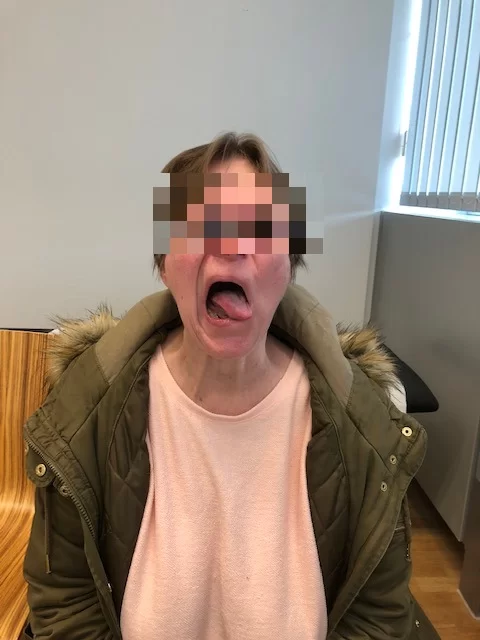

Η μετεγχειρητική εικόνα της ασθενούς ήταν εξαιρετική, χωρίς κανένα νευρολογικό έλλειμα από τις εγκεφαλικές συζυγίες (εγκεφαλικά νεύρα) παρά τη θέση και την έκταση του μηνιγγιώματος.

(Αναπαραγωγή εικόνων με την άδεια της ασθενούς)